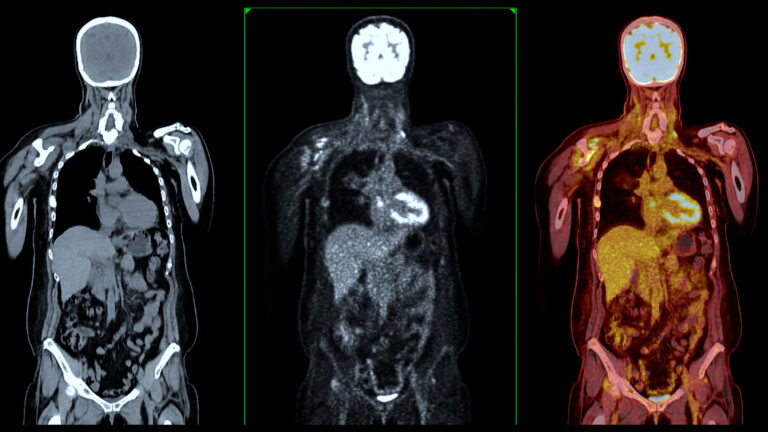

How New Neuroimaging Breakthroughs Are Transforming Brain Science and Clinical Care

Discover neuroimaging innovation transforming clinical practice, from advanced imaging methods to integrated treatment techniques.